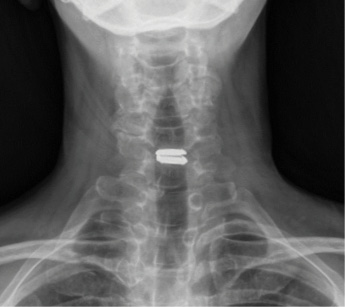

Patient is a healthy, active 58 year-old female, though with advanced degenerative spondylosis at a low cervical level. The patient had favorable anatomy with a long neck and low shoulders to facilitate intraoperative visualization. Fusion was appropriate in this case, but intraoperatively, though we were prepared for this possiblity, the disk space was well-preserved and mobilized without major modification of the endplates. The postoperative flexion and extension radiographs showed movement at the spinous processes of C6/7 and good function of the prodisc C Vivo prosthesis. The adjacent C5/6 level also shows degenerative spondylosis. By optimizing the mobility of the C6/7 level I anticipate the patient will have an improved trajectory for her cervical spine function throughout her life.